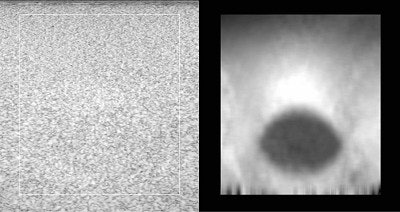

| A phantom with an 8-mm diameter spherical target that is three times stiffer than its background. The target is not visible in the standard B-mode ultrasound image (left), but is obvious in the strain image (right). |